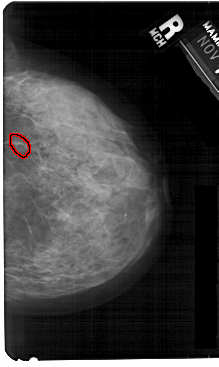

FILE: A_1367_1.RIGHT_MLO.OVERLAY

TOTAL_ABNORMALITIES 1

ABNORMALITY 1

LESION_TYPE CALCIFICATION TYPE FINE_LINEAR_BRANCHING DISTRIBUTION CLUSTERED

ASSESSMENT 4

SUBTLETY 3

PATHOLOGY BENIGN

TOTAL_OUTLINES 1

BOUNDARY